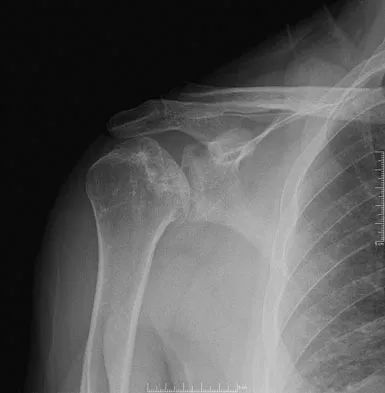

Figures 10a and 10b show the radiographs of a 47-year-old man who reports pain in both shoulders. He has a history of leukemia that was treated with chemotherapy and high-dose cortisone. What is the most reliable treatment option for pain relief in this patient?

Explanation

The radiographs reveal osteonecrosis with collapse. The most reliable and durable treatment for osteonecrosis of the humeral head remains prosthetic shoulder arthroplasty. Osteonecrosis of the humeral head may be seen after the use of steroids, and there is an increasing demand for shoulder arthroplasty in young people because of the use of high-dose steroids in chemotherapy regimes for the treatment of malignant tumors. The indications for most shoulder arthrodeses today include posttraumatic brachial plexus injury, paralytic disorders in infancy, insufficiency of the deltoid muscle and rotator cuff, chronic infection, failed revision arthroplasty, severe refractory instability, and bone deficiency following resection of a tumor in the proximal aspect of the humerus. Clearly, the role of arthroscopy and related minimally invasive techniques in the treatment of humeral head osteonecrosis remains unknown. Hasan SS, Romeo AA: Nontraumatic osteonecrosis of the humeral head. J Shoulder Elbow Surg 2002;11:281-298. Hattrup SJ: Indications, technique, and results of shoulder arthroplasty in osteonecrosis. Orthop Clin North Am 1998;29:445-451.